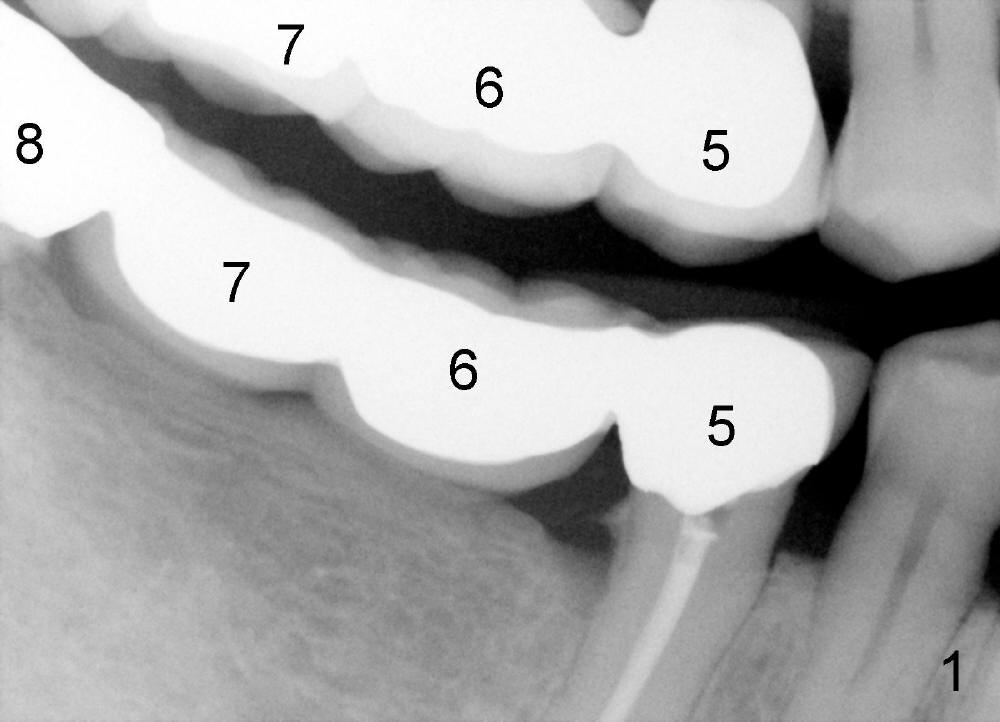

陈先生五十来岁,牙齿不好,右上有一个三个单位桥(图一:5-7),右下四个单位桥(5-8)。五年前他第一次来诊所时左上7有牙髓炎症状(图二),那颗牙齿有很大银汞充填物(A),之下出现龋齿(*)。出于救死护伤精神,开始做根管治疗(图三:*牙胶尖),当时他原来牙医出差了,之后给左上7戴上牙冠(图四:C)。其实图四X光片拍摄是在左上7根管治疗之后一年半,这次左上5有牙髓炎症状,再次为他做根管治疗(图五:*)。他又很久才回来:两年半,这次问题更严重:左上7断了(图五),好在他毫无怨言,可能与他是修理工有关,牙齿也需要修修补补。他也知道现在必须做植牙,这时我们非常自豪告诉他我们能做植牙,他便回家凑钱。一年半后他又从天降,左上问题还没有解决,右下8基牙在桥下出现龋齿(图六:^),必须拔除,这时右下6,7必须先做植牙(图六:植牙设计;N:下齿槽神经; L:颏神经襻(loop))。末端缺牙做活动义齿效果不好,据研究表明它只能恢复百分之十咀嚼功能,而植牙百分之百。